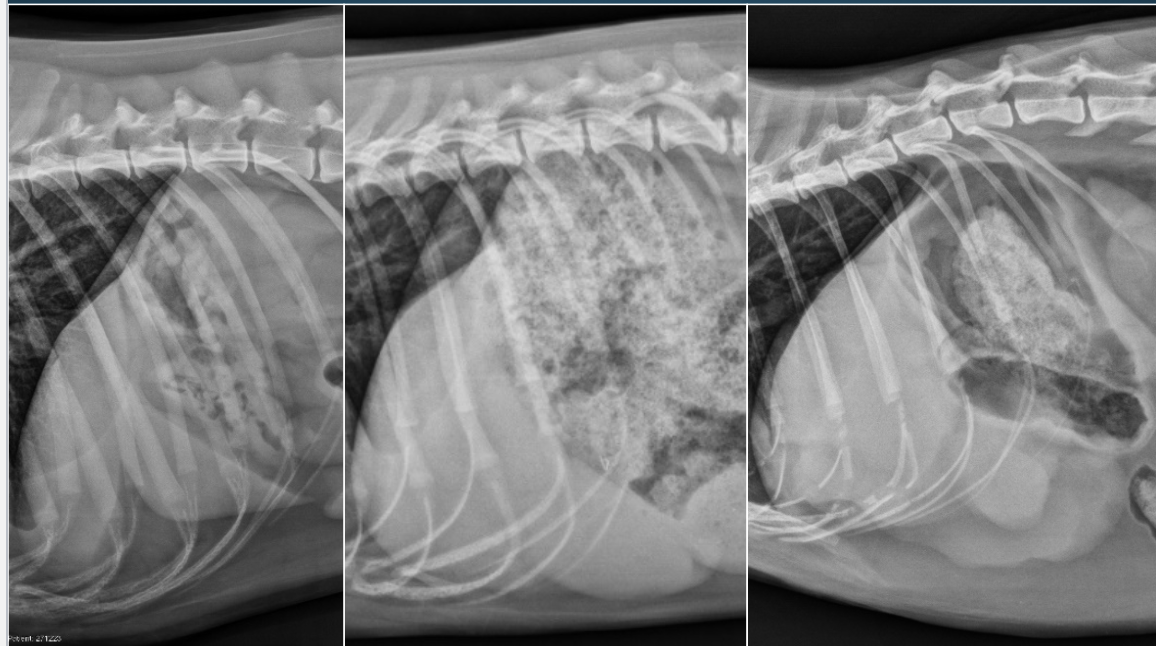

What is shown in these images?

A

normal liver; normal gastric axis